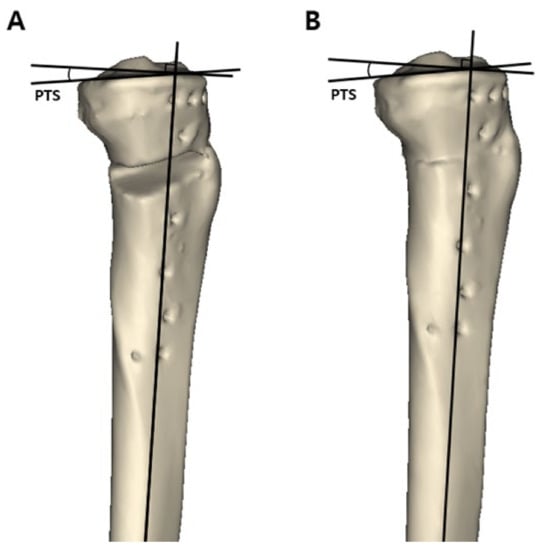

After approval by the institutional review board of our institution, patients with medial compartment osteoarthritis who underwent MOWHTO between May 2011 and November 2017 were retrospectively reviewed. A total of 169 knees were treated with MOWHTO during the study period. Patients who met the following criteria, including the surgical indications of MOWHTO, were included in the study: (1) symptomatic medial compartment osteoarthritis with Kellgren-Lawrence grade III or more, (2) varus deformity of the lower extremity >5°, (3) preserved cartilage in the lateral compartment (International Cartilage Repair Society [ICRS] grade [20] I or II), and (4) age of <65 years. Patients with the following criteria were excluded from the study: (1) patients who did not have a postoperative computed tomography (CT) scan for the full length of the tibia and reconstructed 3D model; (2) a history of previous surgery on the affected knee; and (3) the presence of ligament injury on the affected knee. After applying the inclusion and exclusion criteria, 80 knees were included in this study. The patients were divided into two groups according to the osteotomy inclination angle in the sagittal plane in the 3D model reconstructed CT scan images. When the osteotomy line was inclined anteriorly with respect to the medial tibial plateau line, the cases were classified into group A (Figure 1A), while when the osteotomy line was inclined posteriorly with respect to the medial tibial plateau line, the cases were classified into group P (Figure 1B). Group A and group P consisted of 58 and 22 patients, respectively.

Three major variables were measured in the 3D reconstructed model: (1) the preoperative and postoperative posterior tibial slope, (2) osteotomy inclination angle relative to the medial tibial plateau line in the sagittal plane, and (3) anterior and posterior opening gap and the ratio of these two osteotomy gaps. To measure the posterior tibial slope and osteotomy inclination angle in the sagittal plane, the 3D reconstructed model was aligned in a true lateral position. The true lateral position of the tibia was obtained by manipulating the femoral lateral and medial condyles to be superimposed on the basis of the method presented in a previous study [24]. When measuring variables, the 3D model of the femur was made invisible for convenience. After the true lateral view was completed, this view was captured because these two lines could not be located on the same plane. The posterior tibial slope was measured on the captured 3D true lateral view as previously described [25,26]. The line perpendicular to the bisecting line of the tibial shaft and the medial tibial plateau line were drawn. The angle formed by these two lines was defined as the posterior tibial slope (Figure 2A). To measure the preoperative original posterior tibial slope, the original tibia model was obtained by removing the osteotomy gap of the proximal tibia. The proximal and distal parts of the tibia were combined to the preoperative original tibia by rotating the proximal segment using the lateral cortex as a hinge. The original posterior tibial slope was measured in the same way (Figure 2B). To measure the osteotomy inclination angle in the sagittal plane, a medial tibial plateau line and a sagittal osteotomy line on the anteromedial aspect of the lowermost part of the proximal tibia segment were drawn on the captured 3D true lateral view. The angle formed by these two lines was defined as the osteotomy inclination angle (Figure 3A) [19]. When the front of the osteotomy line was inclined downward with respect to the line parallel to the medial tibial plateau, it was classified as positive, and if it was inclined upward, it was classified as negative. The osteotomy gap ratio was defined as the ratio between the distances of the anterior opening gap and posterior opening gap in the 3D reconstructed model. The anterior opening gap was measured at the medial edge of the frontal plane osteotomy site. The posterior opening gap was measured at the most prominent posteromedial edge of the tibia (Figure 3B) [17,27]. The osteotomy gap ratio (%) was calculated by dividing the anterior opening gap by the posterior opening gap and multiplying by 100. Measurements of variables were conducted by two independent orthopedic surgeons who did not participate in the MOWHTO and were blinded to the patients’ information to increase their reliability. The mean of the two numerical values was used.

Figure 1. The patients were divided into two groups according to the osteotomy inclination angle in the sagittal plane in a three-dimensional reconstructed model. On the true lateral view, a black dotted line was drawn as a medial tibial plateau line. A black solid line was drawn as a sagittal osteotomy line on the anteromedial aspect of the lowermost part of the proximal tibial segment. The angle (α°) formed by these two lines was defined as the osteotomy inclination angle. (A) Group A, the osteotomy line is inclined anteriorly with respect to the medial tibial plateau line. (B) Group P, the osteotomy line is inclined posteriorly with respect to the medial tibial plateau line.